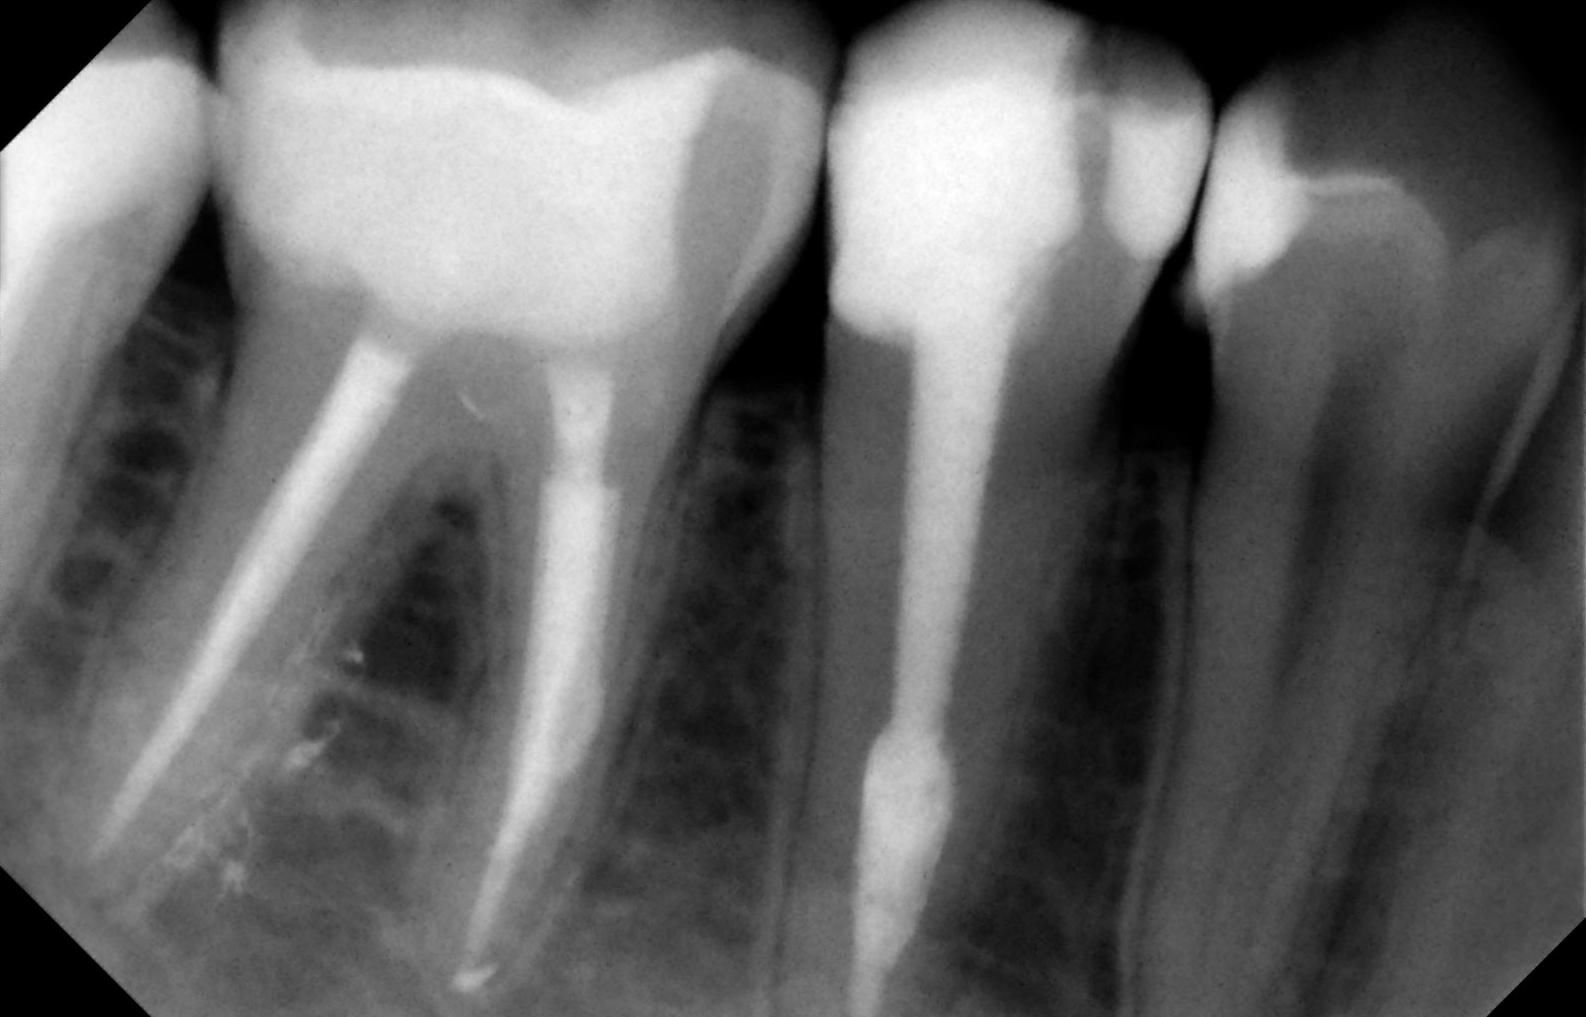

Para la realización de una endodoncia es necesario anestesiar la zona en la que se va actuar. Posteriormente se realiza un agujero en la corona del diente para poder acceder a la pulpa y extraerla y proceder a la limpieza del conducto antes de realizar la obturación y sellado del mismo y de la corona con materiales específicos. Al final de la intervención el diente quedará plenamente insensibilizado y aislado de cualquier otra parte del organismo.

Cuando el diente está muy debilitado se coloca una corona y un perno para devolver la resistencia y la anatomía perdida. Será necesario un seguimiento posterior para verificar la efectividad y evolución de la endodoncia a pesar de que en nuestra clínica contamos con un porcentaje de éxito muy cercano al 100%.